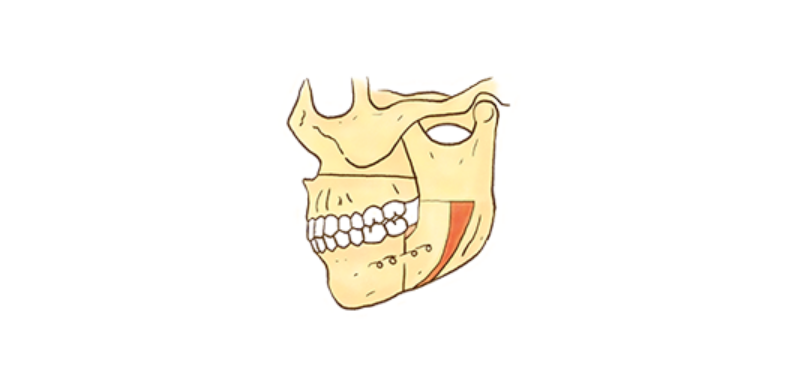

• Dental Implant Process image3

수술을 위한 교정 치료

주걱턱, 무턱증, 안면 비대칭 등 턱뼈 자체의 부조화가 심한 경우 치열교정만으로는 치료가 어려운 경우도 있습니다. ​​​​​​​

이때는 치열교정과 턱 수술을 병행해야 합니다.

수술 교정

일반 교정 치료만으로는 개선이 어려운 골격을 변화시키는 심미성이 우수한 교정 프로그램입니다.

턱 수술과 교정 치료를 병행하여 치료하는 것으로 주걱턱, 안면 비대칭, 무턱, 돌출입 등과 같은 증례에서 주로 이루어지며,

하악 수술 또는 양악 수술이 시행됩니다.